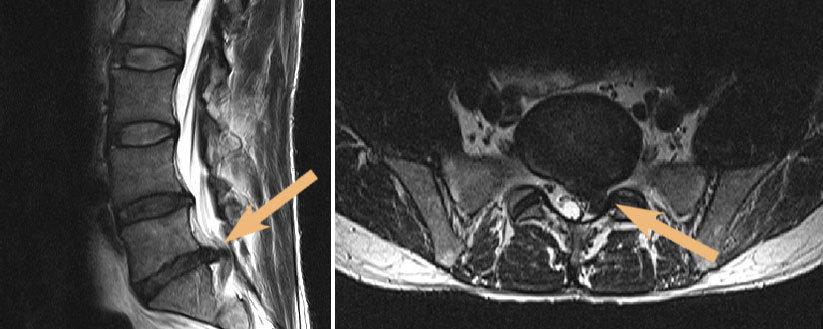

Mit zunehmendem Alter verschlechtert sich automatisch die Versorgung mit Nährstoffen und Wasser, sodass sich die Bandscheiben im fortschreitenden Alter abbauen. Zu einem Bandscheibenvorfall der Wirbelsäule kommt es, wenn der hintere Schutzring der Bandscheibe einreißt oder sich vorwölbt. Dabei können Nerven eingeklemmt und gereizt werden (siehe Abbildungen A und B). Starke Schmerzen und Beschwerden sind die Folge.

Im Anschluss daran werden häufig bildgebende Untersuchungen wie die MRT durchgeführt. Mit der Magnetresonanztomographie (MRT) lassen sich Bandscheibenvorfälle der Lendenwirbelsäule und andere Erkrankungen der Wirbelsäule sehr gut untersuchen und sichtbar machen.